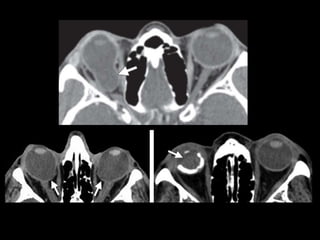

Rotura ocular

• Rotura de la esclera

• Sensibilidad del 56%–68%

– Signos directos:

• Alteración del contorno o volumen (múltiples planos)

• Discontinuidad esclera

– Signos indirectos

• Aumento de profundidad de la cámara anterior

• Aire o cuerpo extraño intraocular

• Mimics

Rotura ocular • Roturade la esclera • Sensibilidad del 56%–68% – Signos directos: • Alteración del contorno o volumen (múltiples planos) • Discontinuidad esclera – Signos indirectos • Aumento de profundidad de la cámara anterior • Aire o cuerpo extraño intraocular • Mimics